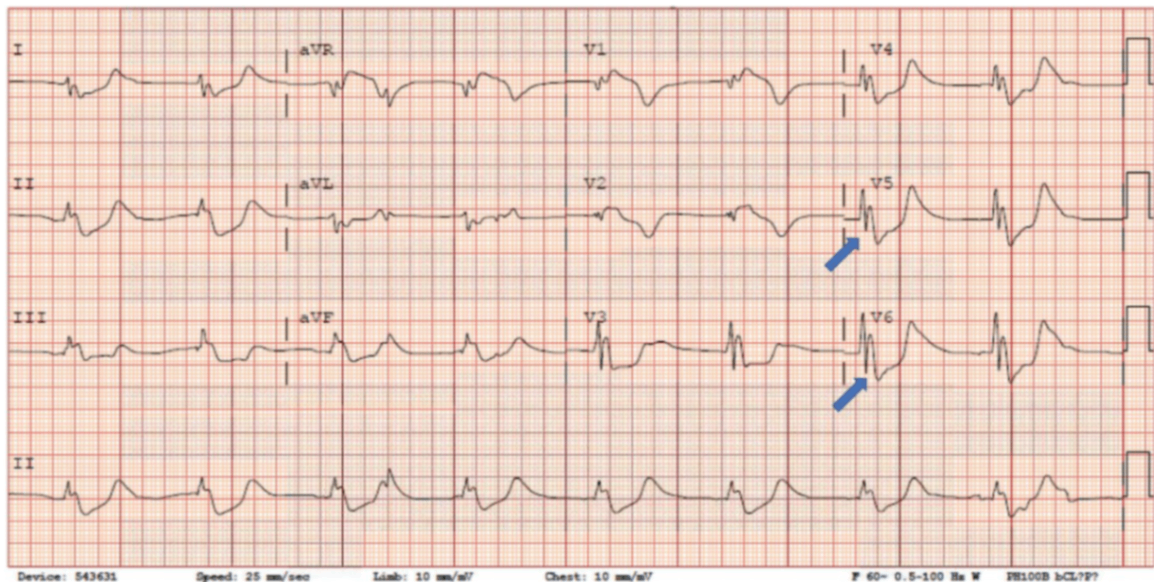

42세 여성이 갑작스런 의식 저하로 인해 응급실로 이송되었다. 환자는 반응이 없으며, 혈압은 78/50 mmHg, 맥박수는 48회/분, 호흡수는 9회/분으로 느리고 얕았으며, 피부는 차갑고 창백했다. 심전도 검사 결과는 다음과 같다. 이 환자에게 가장 적절한 치료 방법은 무엇인가?

• 의식저하, 저혈압, 서맥, 호흡수 저하, 차갑고 창백한 피부를 통해 저체온증을 의심할 수 있다. ECG에서도 화살표 부분에서 J-point에서 Osborn wave가 관찰되고 있어 저체온증이다. 의식이 저하되어 있으므로 최소한 중등도 이상의 저체온증에 해당하며 능동적인 외부 재가온 치료가 필요하다.

• Osborn wave는 32oC 미만의 저체온증에서 주로 보고되고 있다.